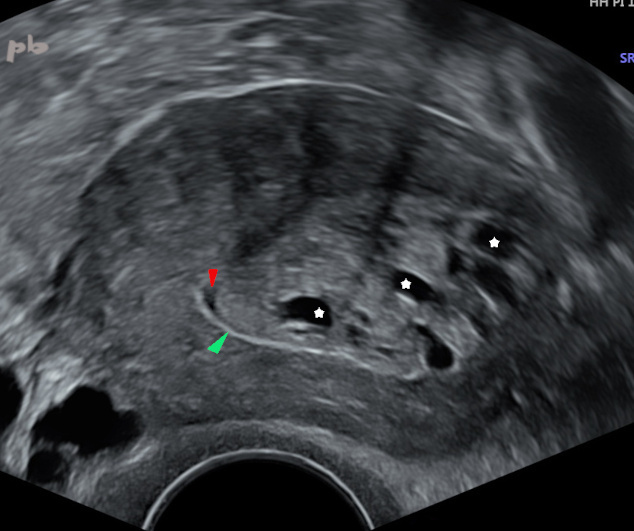

7 – Polyp

Endovaginal ultrasound. Metrorrhagia in a postmenopausal patient without hormone replacement therapy (HRT).

Large, heterogeneous endometrial thickening. Presence of several small internal cysts (white stars). In the lower part of the image, there is a sharp, hyperechoic line (►), consistent with a vacuity line. Combined with the presence of molding by a small amount of fluid (►), this suggests an intracavitary mass.

Large glandular-cystic polyp. Generally, a thickened endometrium and the presence of multiple cysts are highly suggestive of a polyp.